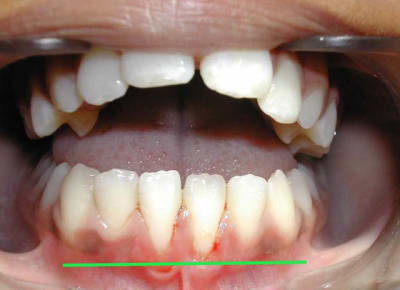

voici l'état de la gencive en fin de TTT. ORTHO

3 kemn9r - Eugenol

La question que je me pose est :

dois-je épaissir cette gencive très fine, (donc fragile), en face de 31/41 ?

@+ Bjc.

bonsoir ,s'il fallait greffer tous les jeunes patients qui finissent l'ortho avec une gencive comme ceci c a d: fine mais pas de tension des freins, on n'arrêterait pas.

maintenant,si on veut appliquer le sacro- saint principe de précaution ......tout est permis